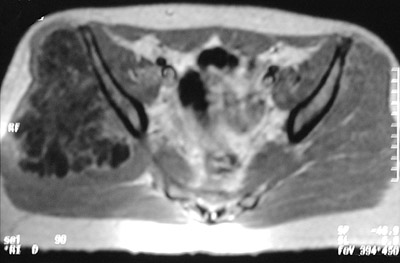

The pelvic MRI scan seen here reveals a mass lesion arising in the right iliac wing that proved to be a chondrosarcoma.